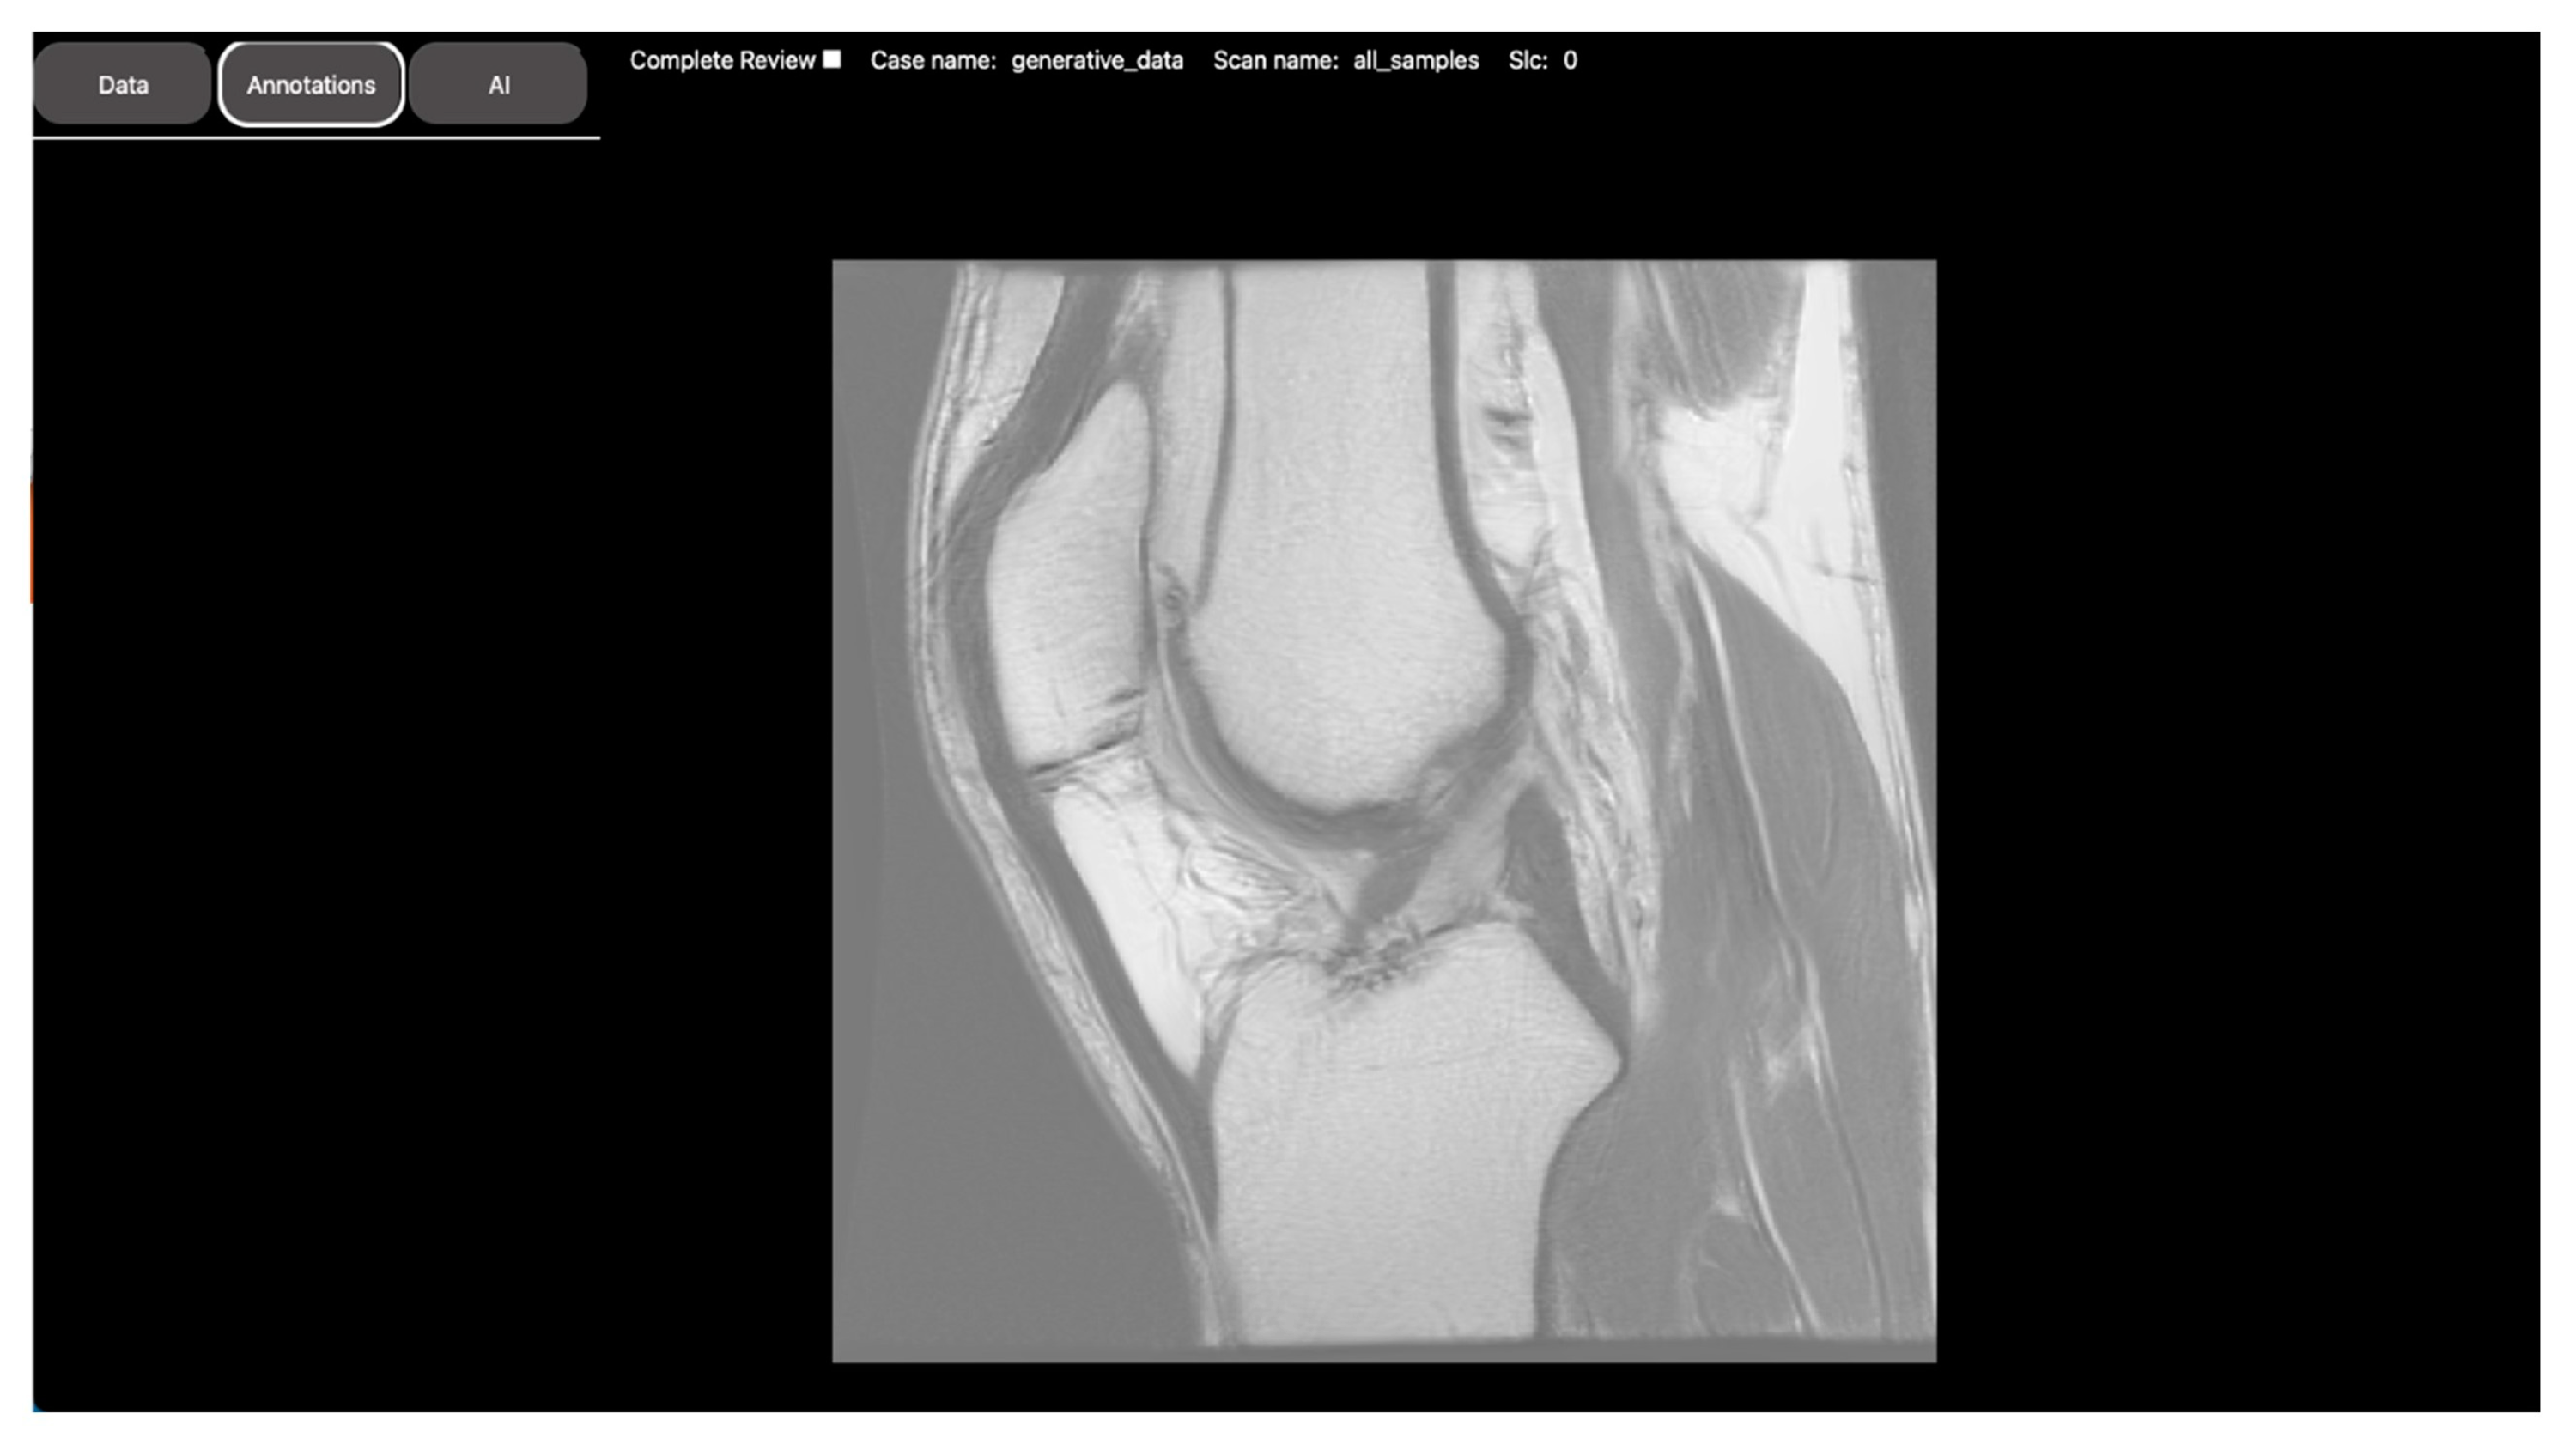

| Objective | Assess the diagnostic image quality of a novel MRI sequence to image the lungs (see Figure 1). | Develop a DL model to automatically identify anatomical landmarks in full leg radiographs (see Figure 2). |